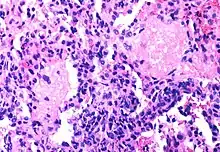

Although the fraction of CD4+ T-cells that is infected with HIV at any given time is never high (only a small subset of activated cells serve as ideal targets of infection), several groups have shown that rapid cycles of death of infected cells and infection of new target cells occur throughout the course of the disease.[41] Macrophages and other cell types are also infected with HIV and serve as reservoirs for the virus.

Furthermore, like other viruses, HIV is able to suppress the immune system by secreting proteins that interfere with it. For example, HIV's coat protein, gp120, sheds from viral particles and binds to the CD4 receptors of otherwise healthy T-cells; this interferes with the normal function of these signalling receptors. Another HIV protein, Tat, has been demonstrated to suppress T cell activity.

Infected lymphocytes express the Fas ligand, a cell-surface protein that triggers the death of neighboring uninfected T-cells expressing the Fas receptor.[42] This "bystander killing" effect shows that great harm can be caused to the immune system even with a limited number of infected cells.